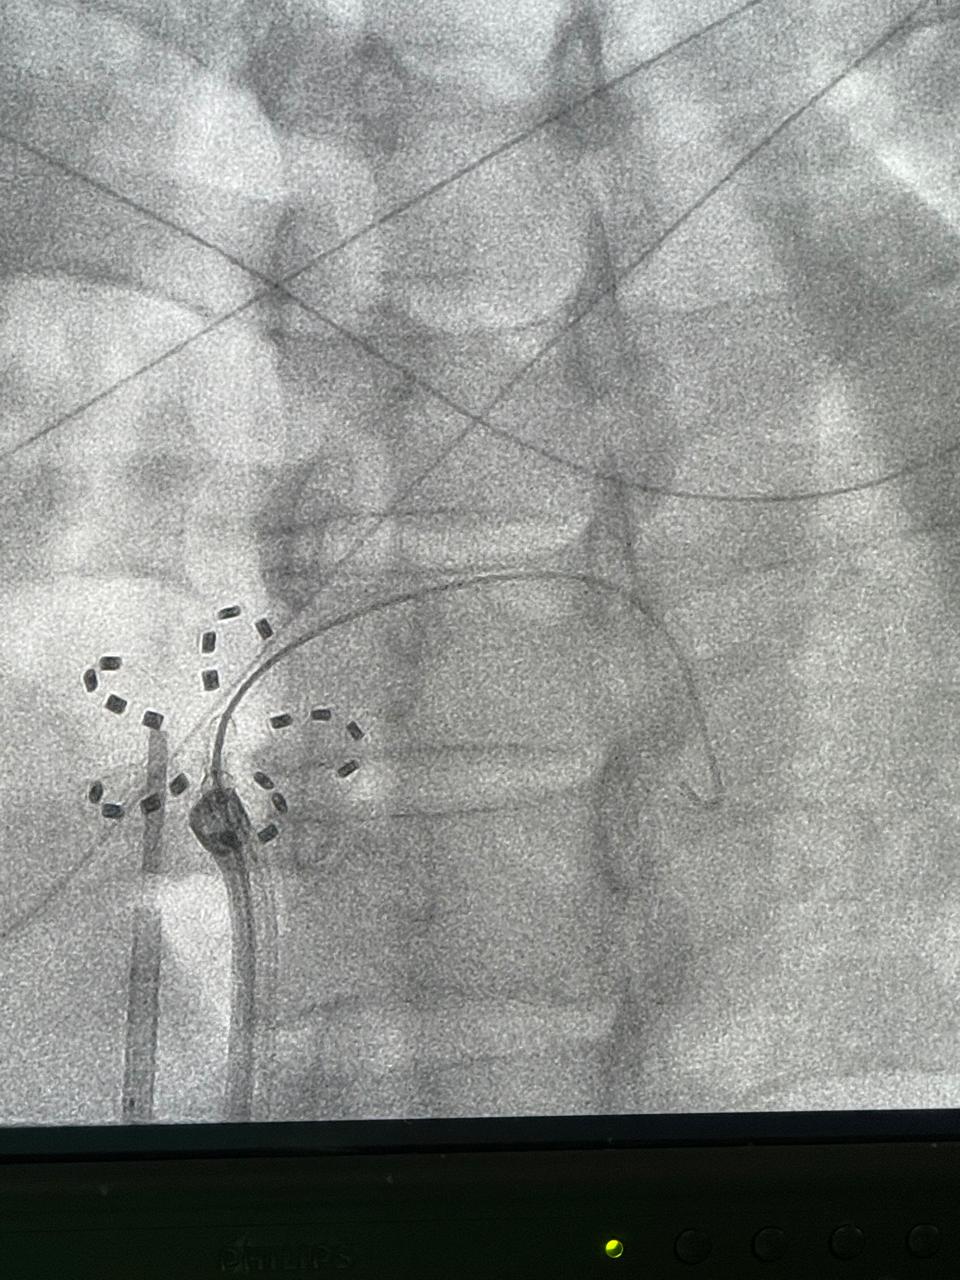

Introducción La punción trans septal es un procedimiento usual en el abordaje...